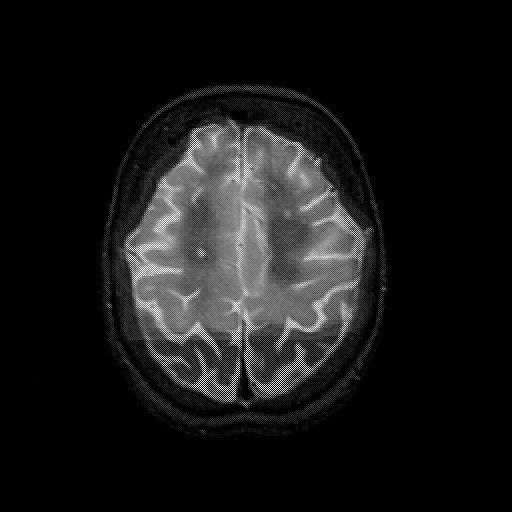

overlay 1: Slice 40

Slice 40

MRCBFCBF with

T1PDT2T1PDT2